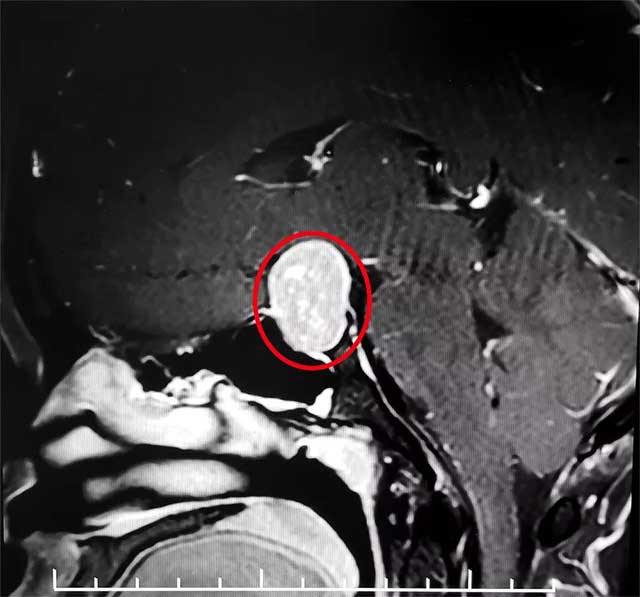

送當(dāng)?shù)蒯t(yī)院就診,經(jīng)醫(yī)院檢查提示泌乳素增高,達(dá)1092μIU/mL,最后頭顱MRI提示垂體腺瘤。

經(jīng)頭顱MRI檢查,患者蝶鞍顯著擴(kuò)大,鞍區(qū)見一腫塊影,大小約15*17*24mm,同時(shí)伴有視力減退、視野缺損。

6B病區(qū)潘仁龍主任指出,患者垂體瘤較大,屬于垂體大腺瘤,已嚴(yán)重壓迫視神經(jīng),手術(shù)指征明確,無明顯手術(shù)禁忌,應(yīng)及時(shí)手術(shù),否則患者視力將嚴(yán)重受損。